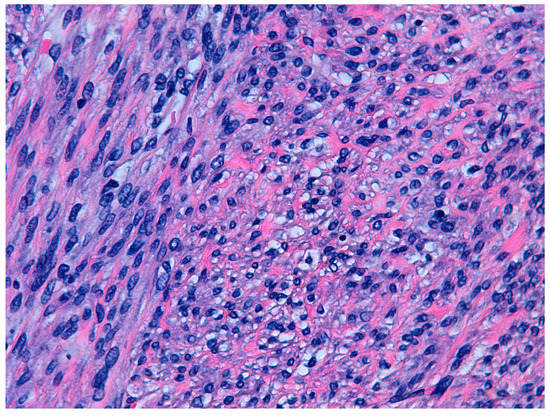

According to the 2014 WHO criteria [9], the pathological diagnosis of STUMP is based on the presence of coagulative necrosis (cases 1 and 4), the finding of 24 mitoses per field and moderate focal atypia (case 2), and diffuse moderate atypia (case 3) (Figure 1 and Figure 2).

Figure 2.

Hematoxilin and eosin staining (40×). Cytological atypia. Case 2.